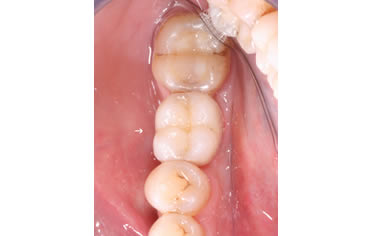

More back teeth replaced by dental implants

Case Five (4 images)